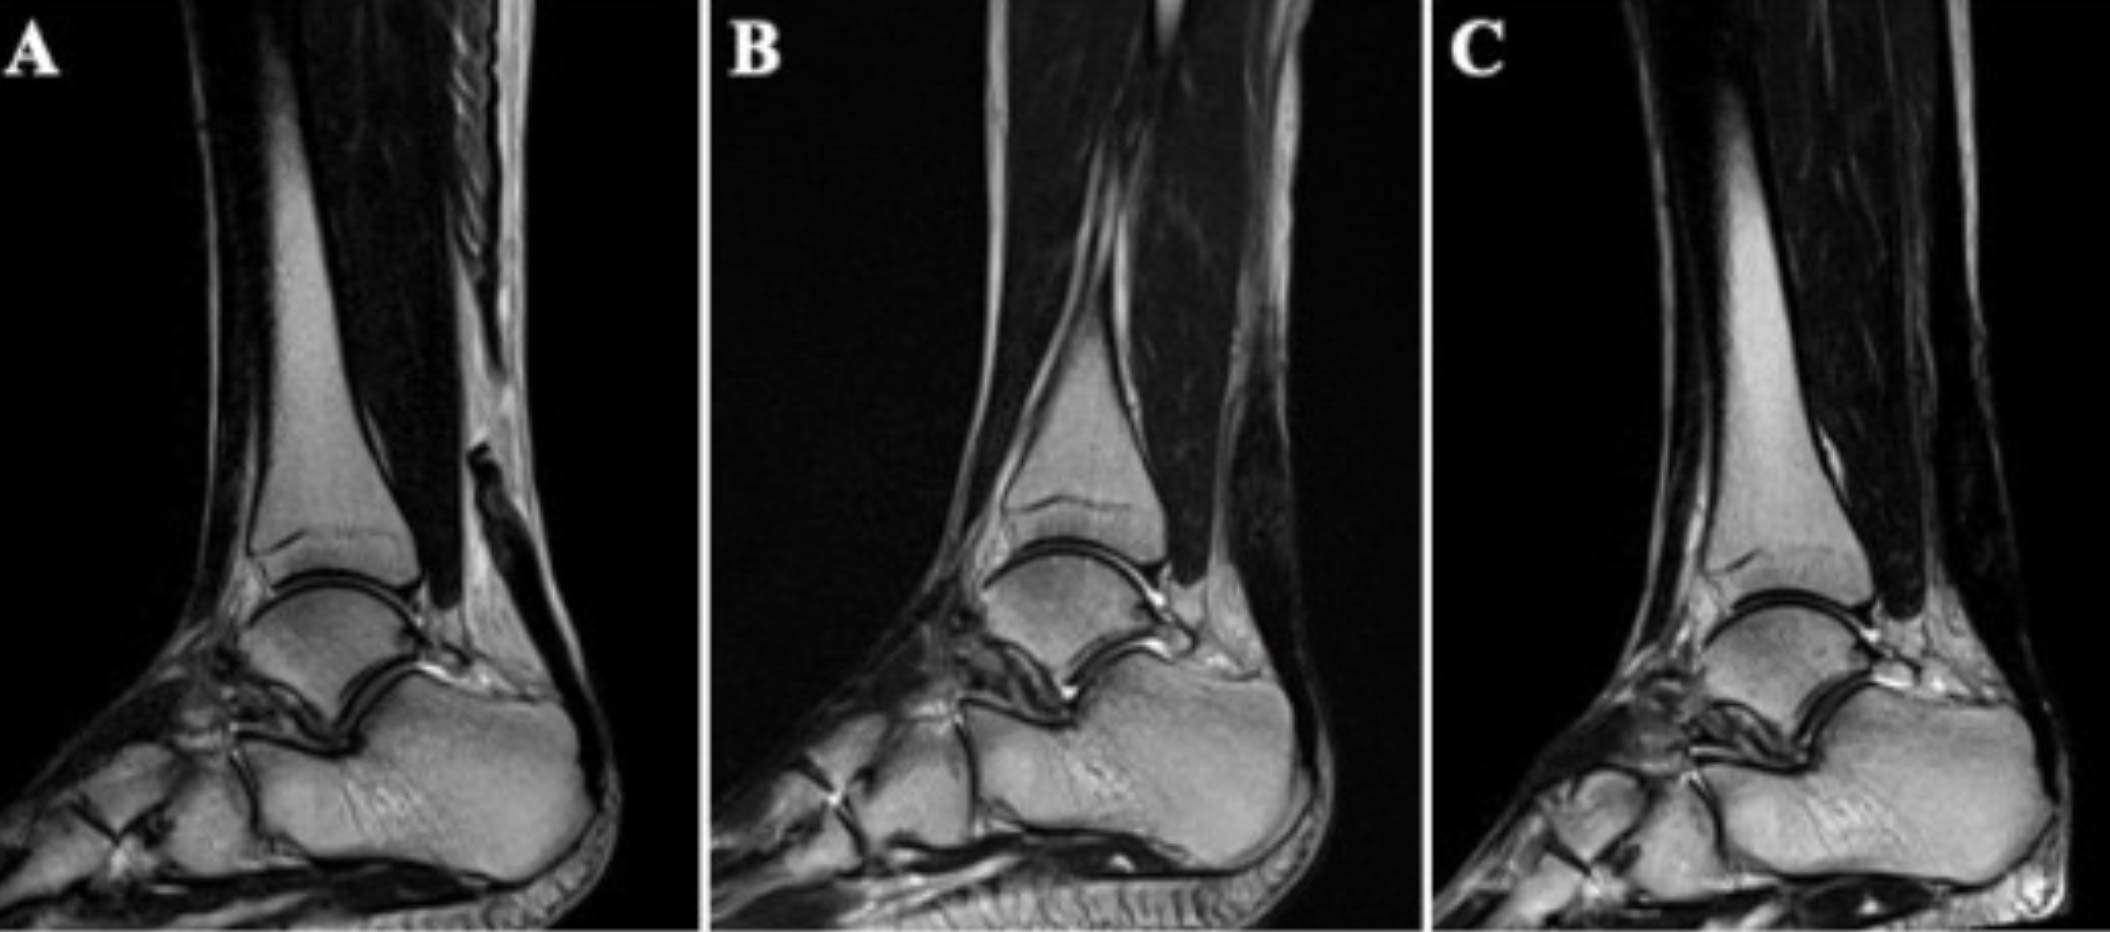

Figure. MRI evaluation detected high signal intensity of the sutured tendon in 25% (2 of 8 patients) at 12 weeks postoperatively and in 0% (0 of 8 patients) at 24 weeks postoperatively. MRI of case 2. Preoperative MRI revealed that the Achilles tendon was ruptured in the mid-substance of the tendon (A). The high signal intensity at the repaired site of the Achilles tendon revealed by MRI taken 12 weeks postoperatively (B) had improved by 24 weeks postoperatively (C).

The 8 patients consisted of 7 male and 1 female athletes with a mean age of 28.5 ± 5.2 years (range, 23-39 years) at the time of surgery. All patients were high-level athletes with a mean Tegner activity score of 9.0 ± 0.5 (range, 8-10). The mean AOFAS score improved significantly from 36.0 ± 9.4 preoperatively to 96.8 ± 3.6 at 1 year postoperatively (P< 0.001). The mean time to be able to perform 20 continuous DHR and 20 continuous SHR was 6.8 ± 0.8 weeks and 10.1 ± 1.6 weeks, respectively. All patients could return to their original sport at preinjury levels with the mean time of 18.3 ± 2.7 weeks. Also, there were no complications related to surgery or injection. Furthermore, T2-weighted MRI showed the high signal intensity of the sutured tendon in 25% (2 of 8 patients) at 12 weeks and 0% (0 of 8 patients) at 24 weeks postoperatively.